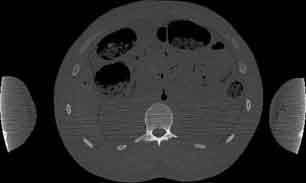

Visible Human male: Sectio transversalis 1605

CT

NMR

Pd                          / T2 \                         T1